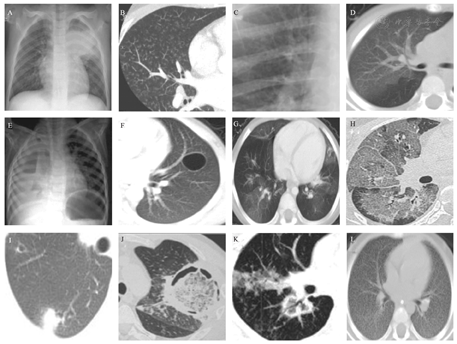

实变和支气管充气征(consolidation and brochogram sign)(图1A):实变是肺泡被填充,形成均匀的密度增高影。可形成大叶性肺炎,常见支气管充气征(不透明的肺部区域内管状气道影),常见于细菌性感染[11]。最常见的病原体为肺炎链球菌、肺炎克雷伯菌,也可见于真菌、结核感染,严重的病毒性感染导致肺实变的非常少见(如SARS、腺病毒感染、甲型流感)。

A.肺实变和支气管充气征;B.小叶中心性结节和树芽征;C.袖口征;D.磨玻璃影;E.气液平征;F.肺大泡;G.马赛克征;H.铺路石征;I.晕轮征;J.空气新月征;K.反晕轮征;L.粟粒样结节。

小叶中心性结节和树芽征(tree-in-bud sign)(图1B):病变累及细支气管及以下的气道,CT上因阻塞而扩张的细支气管形成V型或Y型树枝状,呼吸性细支气管和肺泡管内的黏液实变形成芽,整体类似树芽,是小气道病变非特异性征象。最常见的病原体是金黄色葡萄球菌、大肠杆菌、铜绿假单胞菌、厌氧菌、流感嗜血杆菌、病毒、支原体,也可见于寄生虫感染[12]。

袖口征和轨道征(cuff sign and peribronchial cuffing sign)(图1C):支气管周围病变,导致小叶间隔增厚,支气管壁和支气管周围结缔组织的水肿增厚,影像学横截面见支气管周围环形模糊影,为"袖口征",增厚的支气管壁纵向剖面影像学表现为两条平行线,看起来像火车轨道,称为"轨道征",通常见于肺间质水肿。也可见于引起肺间质病变的病毒(如巨细胞病毒、呼吸道合胞病毒等)和支原体感染。

磨玻璃样不透光影(ground glassopacity)(图1D):为CT上半透明状密度增高影;主要见于病毒、支原体、真菌等感染,细菌性感染少见。

气液平征(air-fluid level sign)(图1E):气液平表明存在肺脓肿或带有支气管胸膜瘘的脓胸。肺脓肿为炎性肿块,中央伴有化脓性坏死,常见内壁光滑或粗糙的空洞,多可见气液平。最常见的病原为金黄色葡萄球菌、肺炎克雷伯杆菌,亦可见于铜绿假单胞菌、厌氧菌[11]。

肺大泡(图1F):为单发或多发薄壁的含气影。常位于肺实变或磨玻璃影中,可引起气胸。肺大泡常见于金黄色葡萄球菌和肺孢子菌感染,也可见于肺炎链球菌等感染。

马赛克征(图1G):也称为马赛克灌注或镶嵌性灌注,为肺密度增高区与密度减低区夹杂相间,呈不规则的补丁状或地图状表现。主要见于闭塞性细支气管炎、哮喘、肺气肿等小气道疾病及卡氏肺孢子虫感染。

铺路石征(crazy-paving sign)(图1H):为CT上磨玻璃样不透明影上重叠有小叶间隔增厚形成的网格影。形似用砖头或石头铺成的道路。磨玻璃影反映了空腔或间质异常,网格影表示小叶间隔或间质增厚、不规则纤维化,伴随肺泡填充的过程。主要见于肺泡蛋白沉积症、肺水肿、腺癌等,也可见于卡氏肺孢子虫感染和新型冠状病毒感染。

晕轮征(halo sign)(图1I):CT上实变的肺结节外缘环绕着磨玻璃样不透明影。主要见于侵袭性肺曲霉菌感染和毛霉菌感染,也可见于新型冠状病毒感染。晕轮征多出现在侵袭性曲霉菌感染的早期[13]。

空气新月征和Monod征(air crescent sign and monod sign)(图1J):为圆形或椭圆形实变肿块影周围新月形气体影。Monod征为空气围绕着真菌球,腔内真菌球具有活动性,落在重力依赖的位置。空气新月征和Monod征常见于侵袭性曲霉菌感染。通常在影像学异常后的2周内出现,并与中性粒细胞功能恢复相一致,出现空气新月征标志着疾病的恢复阶段,预示患儿预后良好[14]。Gefter等[15]研究发现,曲霉菌感染中有空气新月征者较无该征象者存活率更高。Tabone等[13]观察到在发生侵袭性肺部曲霉菌感染的免疫缺陷儿童早期CT出现晕轮征,随后出现空气新月征。但Burgos等[16]研究却发现,与成人不同,儿童曲霉菌感染常不表现出空气新月征或晕轮征。

反晕轮征(reverse halo)(图1K):表现为中央磨玻璃样不透明影周缘被实变影包绕。可见于侵袭性曲霉菌、毛霉菌感染[11],也可见于新型冠状病毒感染。

粟粒样结节(图1L):弥漫性分布的圆形或椭圆形粟粒状密度增高影。以大小均匀、密度均匀、分布均匀的三均匀为特征。多见于血型播散型肺结核。也可见于曲霉、白色念珠菌感染及粟粒样转移瘤。